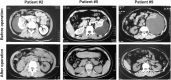

Spontaneous renal subcapsular fluid collection may occur as a rare presentation of nephritic syndrome, and distension of the renal capsula and Gerota fascia due to massive fluid accumulation may cause pain. In addition, hypertension secondary to renal ischemia and activation of renin-angiotensin-aldosterone system may also occur. The objective of this study is to evaluate the surgical outcome of retroperitoneal laparoscopic renal capsulectomy for patients with this disease.We retrospectively analyzed the clinical data of 10 female patients with spontaneous renal subcapsular fluid collection, diagnosed with B ultrasound and enhanced computed tomography (CT) scan. Eight patients first underwent percutaneous renal subcapsular drainage, which seemed to be less effective, and then all patients underwent retroperitoneal laparoscopic renal capsulectomy. The volume of renal subcapsular fluid was documented, the fluid was examined by routine biochemical tests, and the excised renal capsules underwent pathological examination individually. The postoperative drainage time for each patient was documented, and follow-up was conducted 1, 3, 6, 12 months, and 2 years postoperatively.Retroperitoneal laparoscopic renal capsulectomy was successfully performed in all patients with no major complications. The average volume of renal subcapsular fluid was 436 milliliter (mL, 180-880 mL) in light yellow color, and the concentration of creatinine and urea nitrogen was quite similar to that of serum. The pathological findings revealed fibrous dysplasia of the renal capsule with chronic infiltration of inflammatory cells. The average drainage time was 11.5 days (5-30 days) postoperatively. All patients recovered 1 month after the operation and there were no recurrences with a mean follow-up period of 12 months (6-24 months).The reason for spontaneous renal subcapsular fluid collection is unknown, and the aim of treatment is mainly to alleviate symptoms. In our experience, retroperitoneal laparoscopic renal capsulectomy is an effective surgical treatment, especially for patients who were refractory to percutaneous renal subcapsular drainage, with no observed recurrence.